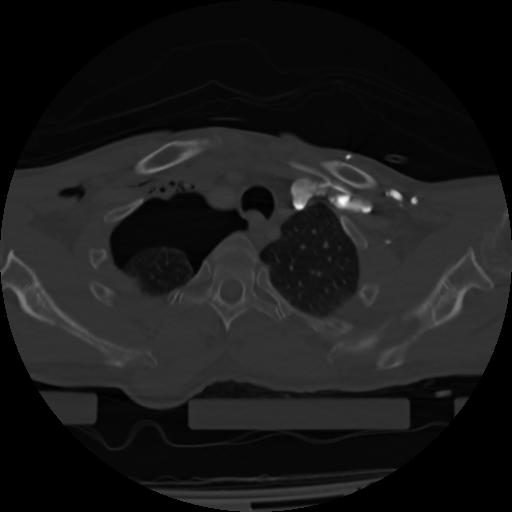

21 ANGIO,CE,Axial,3.0,ANGIO,,